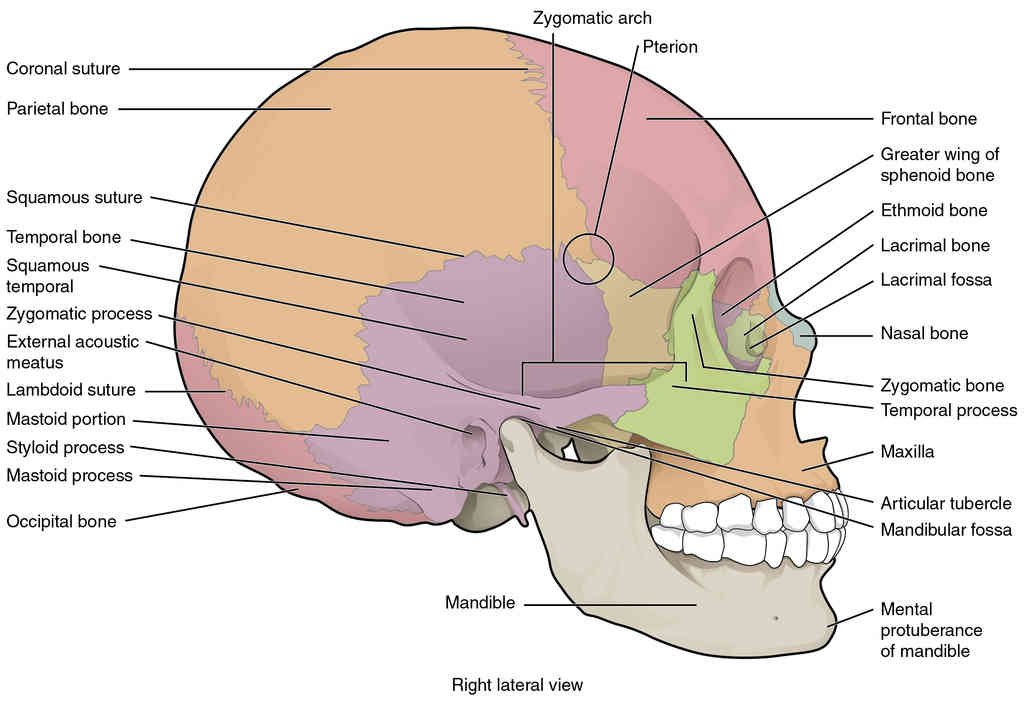

This page is under construction. For now, it is just a resource of the images found in the OpenStax Anatomy and Physiology Handbook. It wil slowly change into a revision tool. Each slide has a number. Use this to refer to the slide. When completed, it will have an unlabelled section, with labelled slides in parallel. On the unlabelled slides, write your answer and use the labelled slide to assess yourself. Keep track by also noting the number on each slide. Improvement at each attempt is important, more so than full marks on a first attempt.